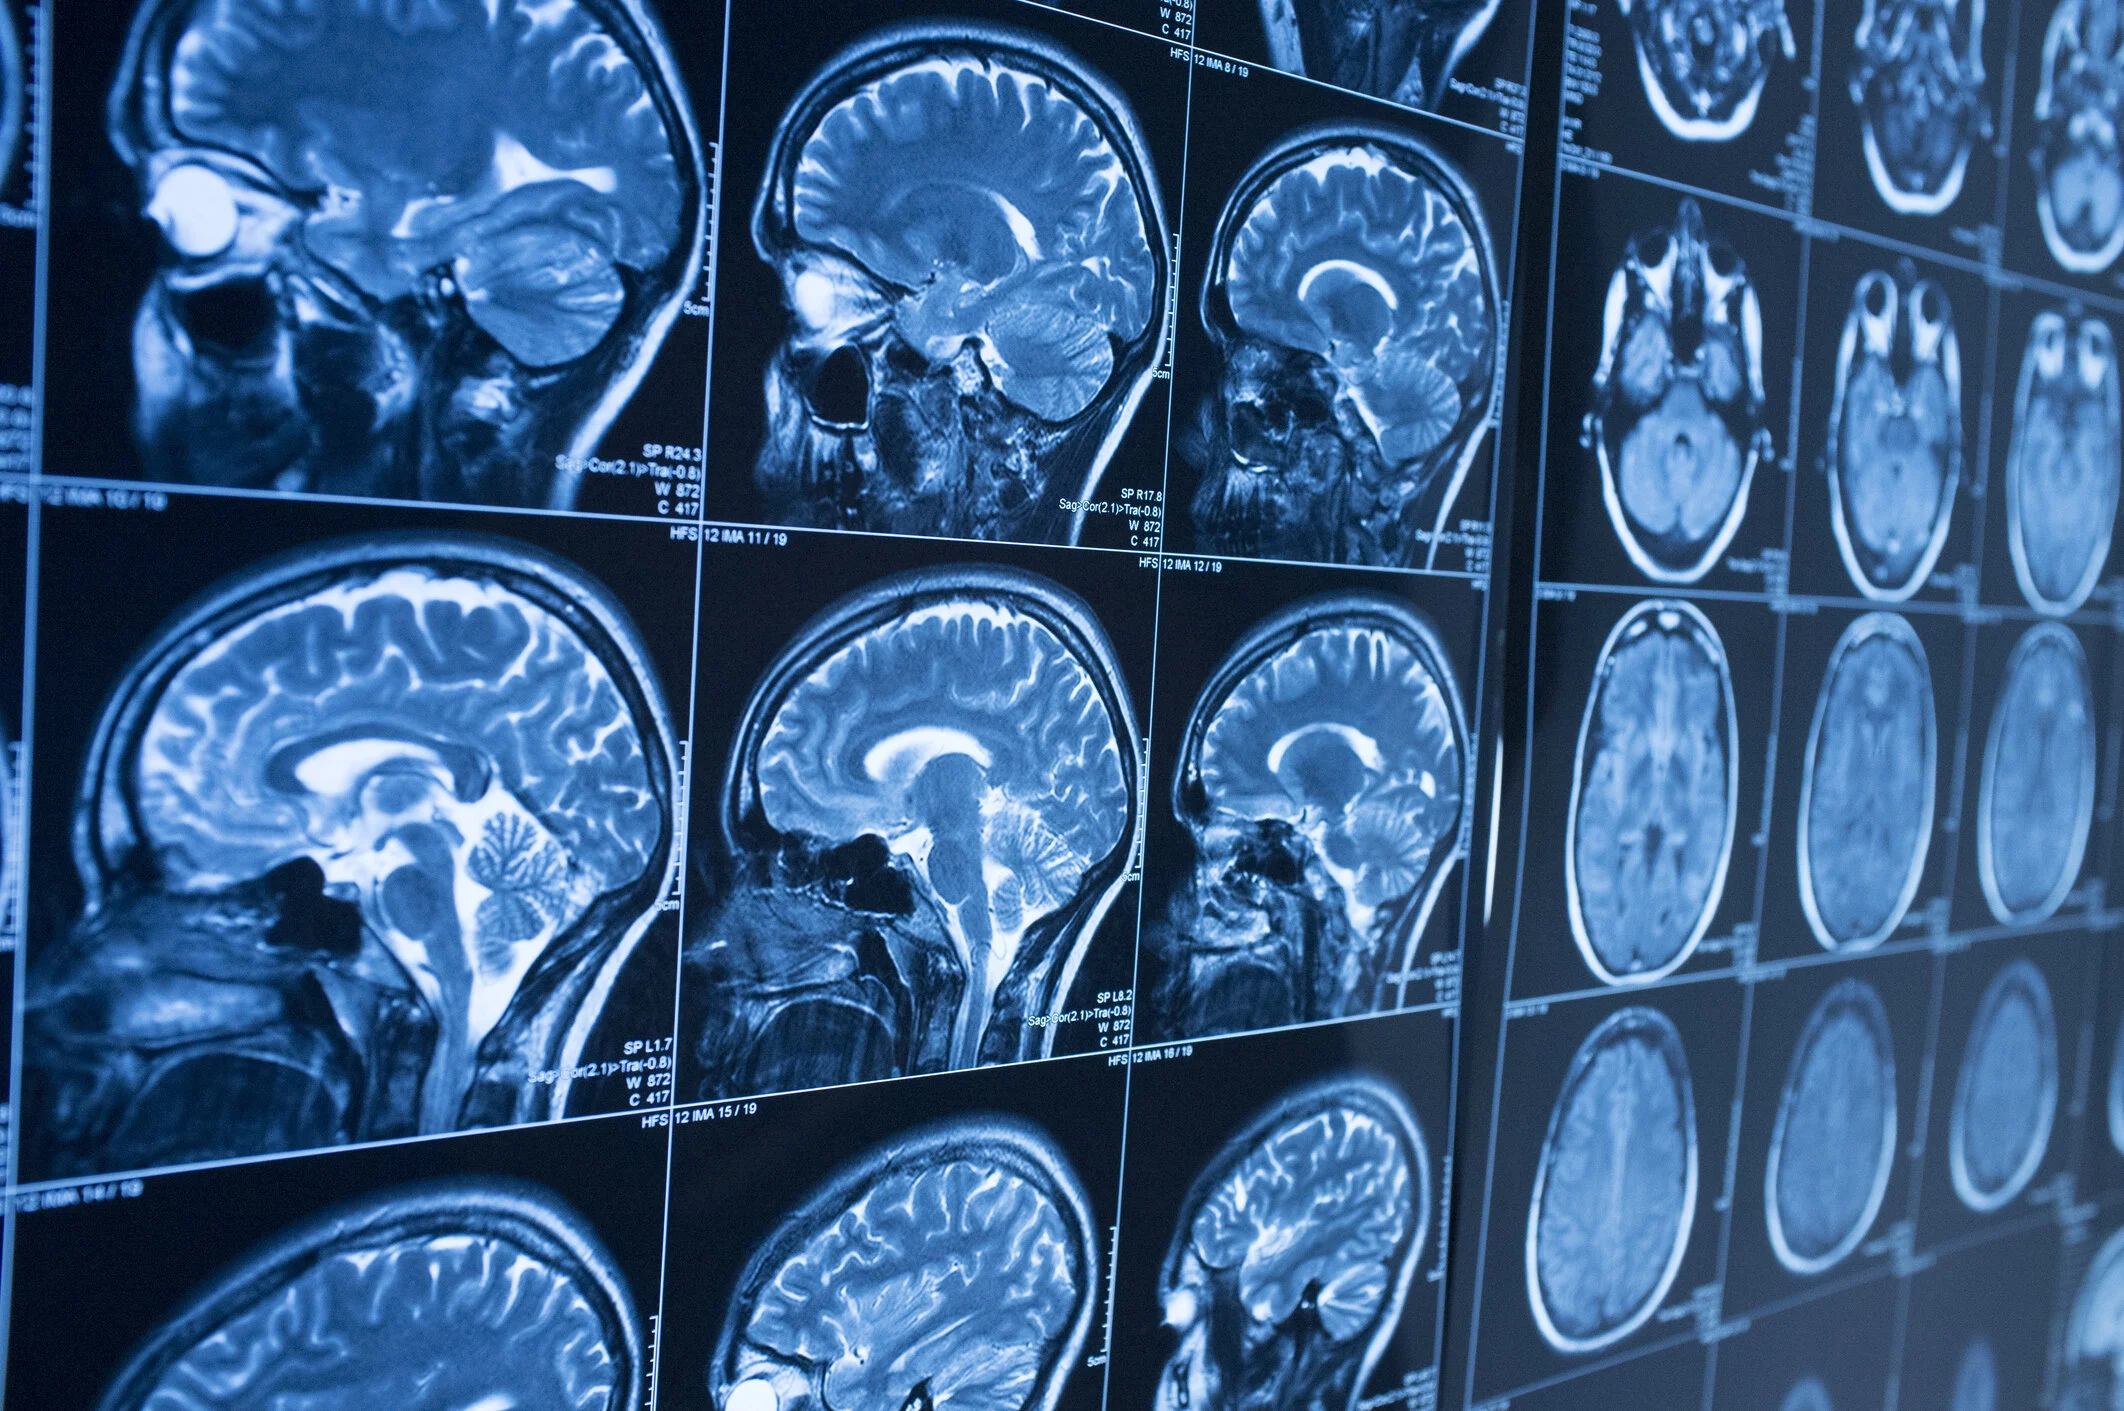

Magnetic Resonance Imaging or an MRI, is a medical imaging technique that uses a strong magnetic field and radio waves to create detailed, cross-sectional images of the internal structures of the human body. Unlike X-rays or CT scans, MRI does not use ionising radiation, making it a non-invasive and safe imaging method.

During an MRI, the patient is placed inside a large, tube-like machine that contains a powerful magnet. Radio waves are directed at the body, causing the hydrogen atoms in the body's tissues to emit signals. These signals are captured by a receiver and processed by a computer to create highly detailed images of the body's soft tissues, organs and structures. MRI is particularly valuable for visualising the brain, spinal cord, joints, muscles, and organs like the heart, liver and kidneys.

MRI can provide essential information for diagnosing a wide range of medical conditions, including neurological disorders, musculoskeletal injuries, cardiovascular conditions and more. It is a versatile tool that helps healthcare professionals obtain detailed images to aid in diagnosis and treatment planning.